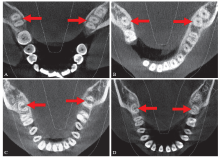

图 4

下颌第二恒磨牙牙根和根管形态的对称性 A:双侧牙根和根管形态对称(双根型);B:双侧牙根和根管形态对称(锥形融合根型);C:双侧牙根形态不对称;D:双侧牙根形态对称而根管形态不对称。"